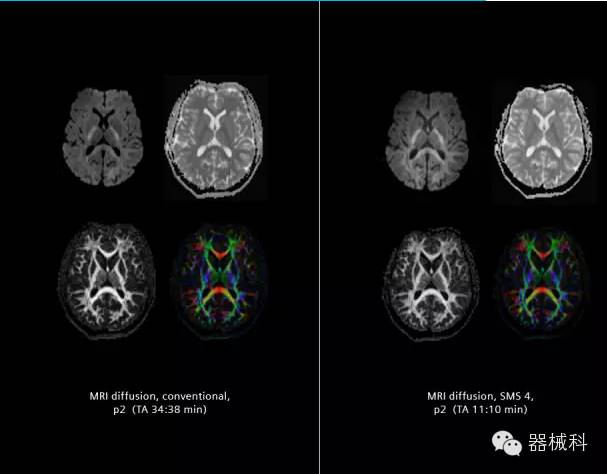

在2015年RSNA上,西門子隆重發(fā)布了Simultaneous Multi-slices 技術(shù)(即同時(shí)多層采集技術(shù),簡(jiǎn)稱SMS),這是磁共振掃描技術(shù)中第一次引入“同時(shí)多層”的概念,此概念技術(shù)的發(fā)布,將對(duì)未來磁共振成像領(lǐng)域帶來巨大的變革!

SMS技術(shù)可以將原本用于科研的高級(jí)成像技術(shù)轉(zhuǎn)化成臨床常規(guī)。

擁有了SMS“同時(shí)多層”采集技術(shù)之后,用戶可以在非常短的時(shí)間內(nèi)完成MR掃描,結(jié)合西門子靜音技術(shù),大大提高患者的舒適性,或在單位時(shí)間內(nèi)采集更多的數(shù)據(jù),也可以得到高精度、高準(zhǔn)確性、大數(shù)量的功能成像數(shù)據(jù),為臨床和科研提供強(qiáng)大的支持。專家認(rèn)為,SMS“同時(shí)多層”采集技術(shù)未來在 提高成像質(zhì)量、外科手術(shù)計(jì)劃、降低術(shù)后神經(jīng)功能缺陷、提高fMRI的時(shí)間采集效率、提高靜息態(tài)功能磁共振數(shù)據(jù)質(zhì)量等方面將帶來深遠(yuǎn)影響,希望該技術(shù)可以盡早面世,引領(lǐng)磁共振進(jìn)入多層時(shí)代!